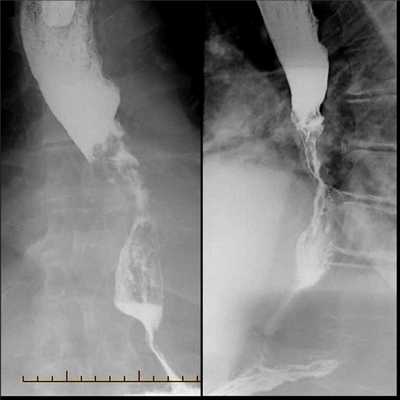

Рентгенологическое исследование пищевода, желудка и двенадцатиперстной кишки с контрастным веществом (сульфатом бария) имитирует прием человеком пищи, при этом за счет приема через рот контрастного вещества «прокрашиваются» измененные участки пищевода. Исследование позволяет наглядно оценить локализацию и протяженность опухолевого поражения органа и степень сужения его просвета.

- Рентгенография с бариевым контрастом. Пациент принимает внутрь сульфат бария, который обволакивает стенки пищевода. Это позволяет увидеть на снимке рельеф стенок и обнаружить сужение просвета. На ранней стадии рак может иметь вид небольших круглых выпуклостей, то есть бляшек. На поздней стадии развития новообразование принимает вид большой опухоли неправильной формы, которая может вызывать сильное сужение пищевода. Рентгенография также позволяет диагностировать трахеопищеводную фистулу, то есть когда из-за разрушения новообразованием стенки пищевода на всю толщину пищевод начинает сообщаться с трахеей.